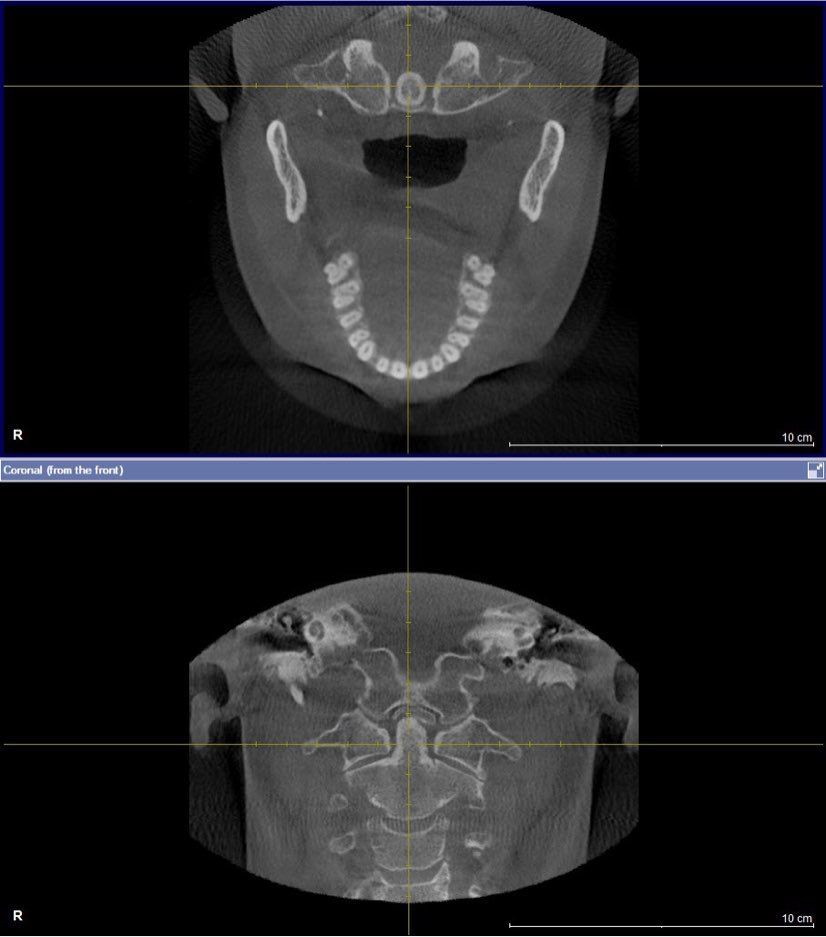

Over 40 million Americans suffer from Myofascial Pain Dysfunction (MPD), a condition that causes headaches and muscular pain. Dr. Klim uses advanced biofunctional diagnostic techniques to decrease painful tension in the head, neck, and shoulder muscles.

Many suffer from Myofascial Pain Dysfunction (MPD) and are not sure of the nature of their condition and how to solve it. You may have heard other terms that describe this condition such as TMJ or TMD. This is short for Temporomandibular Joints. Craniomandibular Dysfunction (CMD) or Temporomandibular Disorder (TMD) are another terms dentist use.